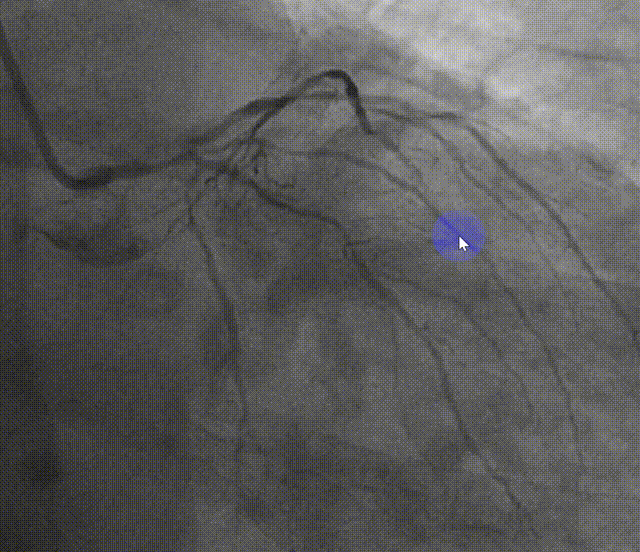

两根工作导丝分别送至LAD和LCX处,使用1.5x15mm和2.5x15mm预扩球囊预扩

于LAD中段置入2.5x26mm支架

3.0x15mmNC球囊高压扩张后LM-LAD支架仍不能通过。

在球囊辅助下,Telescope™延长导管送至LAD中段支架内,LM-LAD支架通过病变